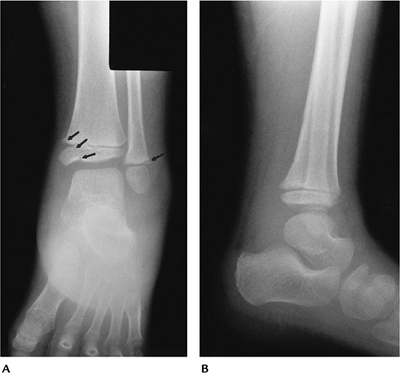

![]() |

FIGURE 6-2 AP (A) and lateral (B) radiographs demonstrating marked swelling with a Salter-Harris Type IV (arrows) tibial fracture and Type II fibular fracture (arrow) as the result of an inversion injury.

P.313

FIGURE 6-3 AP (A) and lateral (B) radiographs of an eversion injury with opening of the tibial physis (arrow) and an incomplete fibular fracture (open arrow).

|